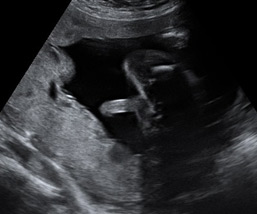

Ecografías de la semana 28 de embarazo

Ecografía semana 28: sexo masculino. La imagen ecográfica muestra los genitales masculinos del bebé. Se puede apreciar el pene y el escroto del niño.